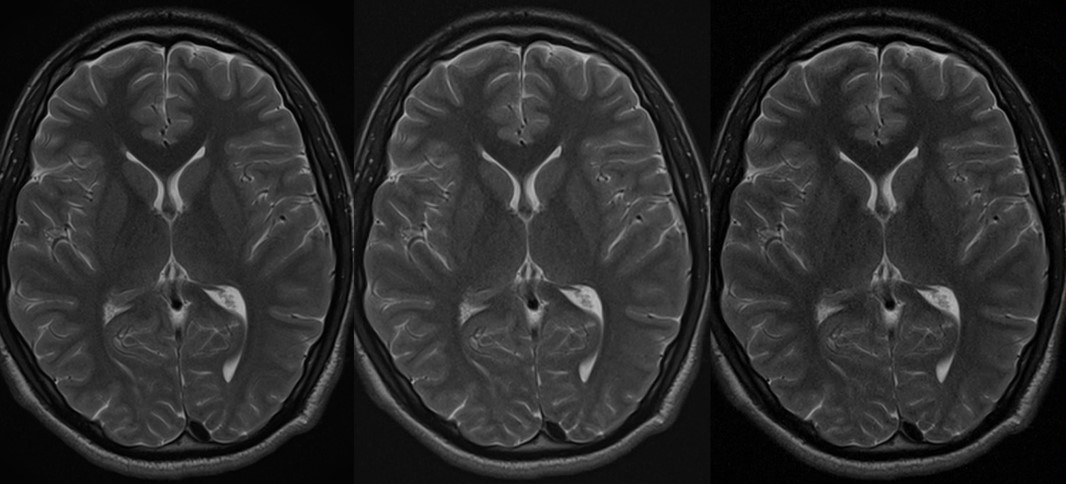

без Compressed Speeder

с помощью Compressed Speeder

Нет ускорения по сравнению с Compressed SPEEDER 2.0

Время сканирования 2:48

Время сканирования 1:24